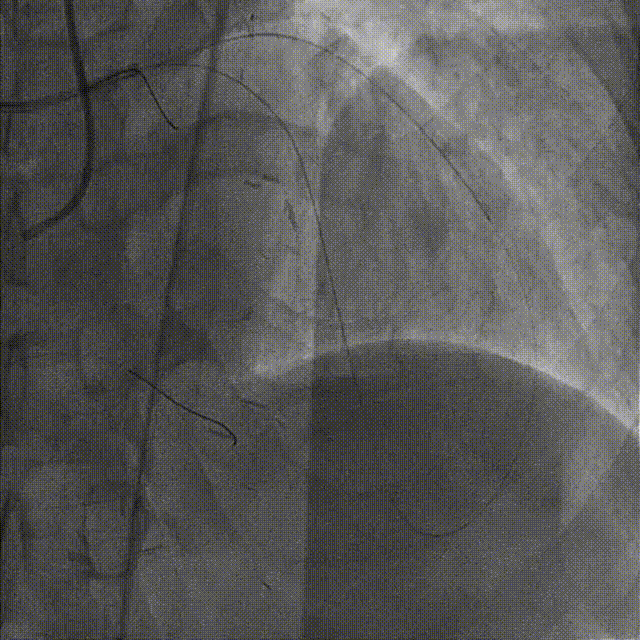

在HighTrack微导管的支撑下及逆向导丝的指引下,正向用Gaia First、Gaia Third、PILOT 200导丝反复尝试,均未能通过闭塞段进入血管真腔。

逆向重新送入一根SION Blue导丝反复尝试,最终进入正向指引导管内,推送逆向微导管至正向指引导管内,逆向送入RG3导丝至正向入口,正向沿RG3导丝推送微导管至LAD远段,撤出逆向导丝及微导管,交换一根SION Blue导丝至LAD远段。

依次用Pinoeer 2.0mm x 15mm、Pinoeer 2.5mm x 15mm球囊至病变处反复扩张,送入Marvel导丝至D1远段做保护,LAD行IVUS检查。